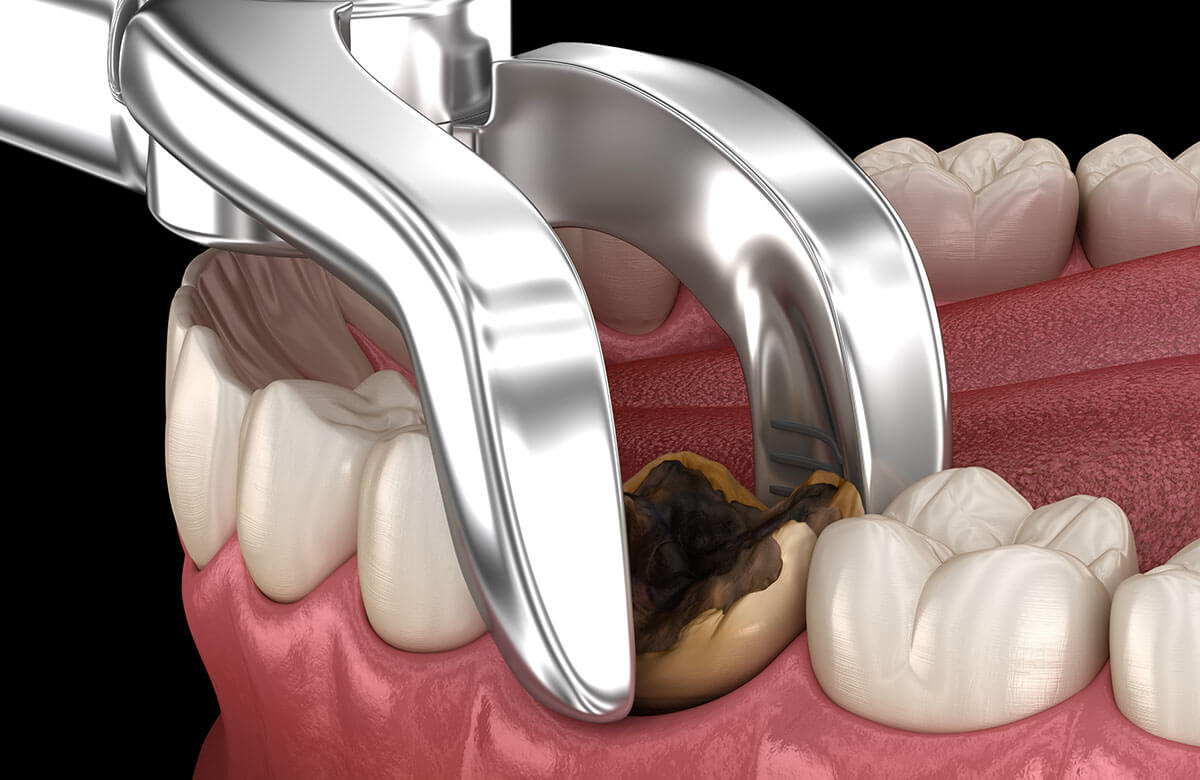

Tooth Extraction Cost For 2021 Procedure Risks Recovery

After getting your tooth pulled you should stick to a diet of soft and liquid foods for the first 24 to 48 hours You should also avoid hot foods and drinks as the heat can cause During the first 24 hours after tooth extraction you can only eat soft foods and drink liquids without a straw This helps you avoid any problems and complications after the